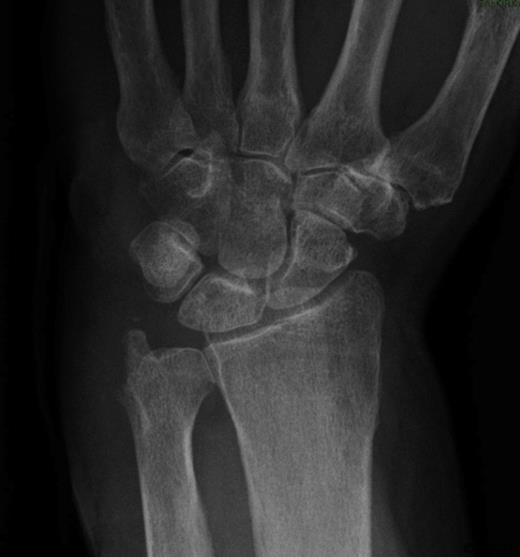

She presented again at the orthopaedic clinic 26 months later with continuing swelling and pain. Ultrasound showed a synovial tumour on the dorso-medial aspect of the wrist (Figure 1). Aspiration of the cyst produced a small amount of pus. She was admitted for incision and drainage of the abscess. Microscopy of the tissue showed a granulomatous inflammation.

Ultrasound showing a synovial tumour on the dorsal medial aspect of the wrist